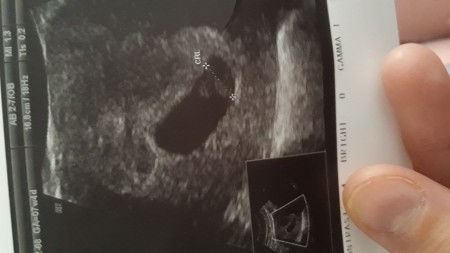

7+6 haftalık burda merak ediyorum

Evet arkadaşlar kızmı erkekmi hani anlayan arkadaşlar oluyormuş